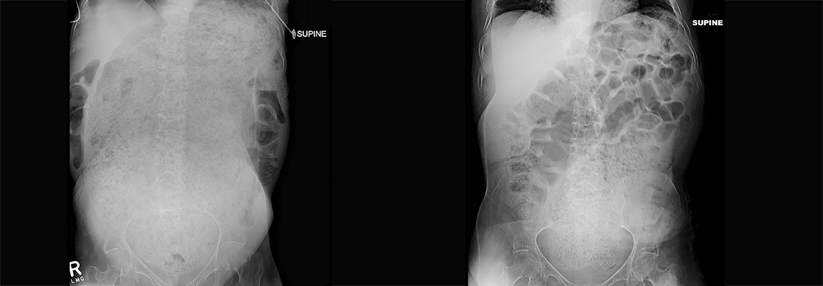

Eine chronische Verstopfung kann das Rektum immens vergrößern und dadurch eine OP erforderlich machen. Dies zeigt die Kasuistik einer Seniorin, die…